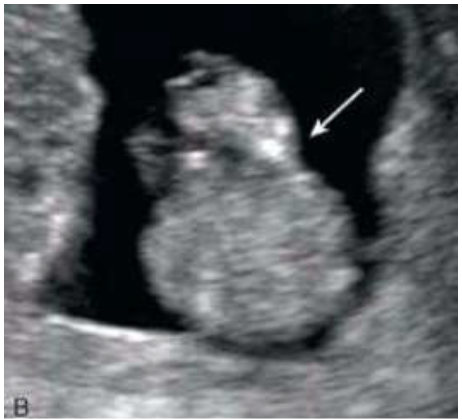

III - As estruturas assinaladas na imagem abaixo, correspondem ao diencéfalo (1) e ao tronco cerebral/ponte e bulbo (2).

IV - A imagem deve estar ampliada de maneira que apenas a cabeça e a parte superior do tórax sejam vistas.